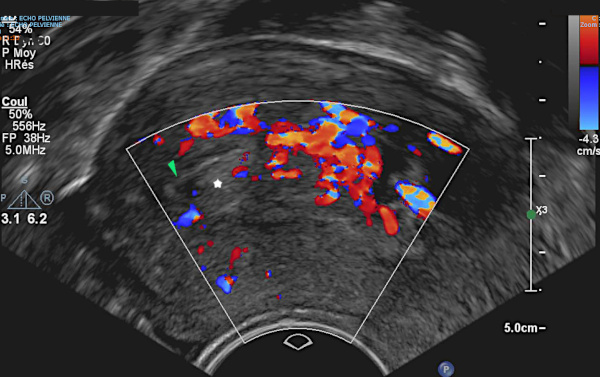

13 – Polypes multiples – Echographie vaginale

(même patiente que 12)

L’échographie complémentaire retrouve un endomètre hétérogène. Il existe un peu de liquide permettant de constater que l’endomètre est fin en réalité (►).

Ce liquide moule également une image hyperéchogène ovalaire (étoile blanche) : polype.

L’épaississement de la cavité est en rapport avec les nombreux polypes. Nombreux pédicules vasculaires en doppler.